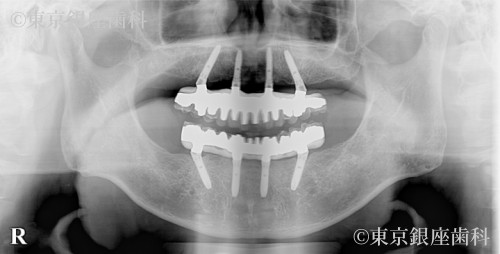

高額見積もりからセカンドオピニオンで最適治療を選択し噛める機能を獲得した80歳代男性の症例

施術内容 ワンデイインプラント

他院で1500万円超の提案を受け不安になり当院受診。精密診断の結果、片顎4本で十分と判断し上下ワンデイを実施。禁煙にも成功し現在も安定。

上下ワンデイインプラント